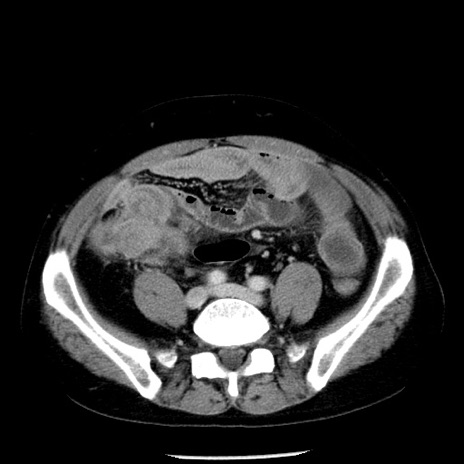

冠状断像

【症例】40歳代男性

【現病歴】2日前から胃痛あり。徐々に周期的な激痛に変化した。本日になっても激痛があるため受診。

【身体所見】意識清明、BT 38-39℃台あり、腹部:膨満、やや硬、右下腹部に圧痛あり。

【データ】WBC 8500、CRP 23.26